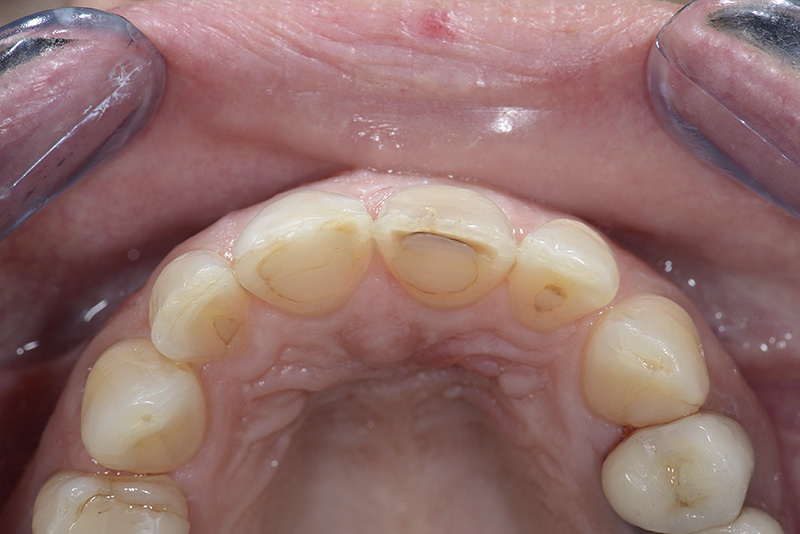

PREMESSA: in seguito all’estrazione dell’incisivo laterale superiore di destra, resasi necessaria per cause batteriche, si decide di affrontare il caso con il posizionamento di un impianto in sostituzione dell’elemento mancante dopo guarigione del sito infetto. Con tecniche rigenerative sia dei tessuti ossei mancanti a causa dell’infezione pregressa, sia dei tessuti gengivali che appaiono inizialmente troppo spostati in alto, si ripristina una corretta morfologia delle parabole (contorni) gengivali e delle papille interdentali (triangoli di gengiva tra due denti vicini).

Vengono utilizzati 2 tipi di provvisori: il primo, cementato ai denti vicini, viene utilizzato dal momento dell’estrazione del dente fino ad impianto osteointegrato (circa 6 mesi); il secondo, avvitato direttamente all’impianto, ha una funzione di prova estetica ma soprattutto di guida per la maturazione dei tessuti gengivali peri-implantari portandoli verso la maturazione completa prima di posizionare la corona finale in disilicato di litio.